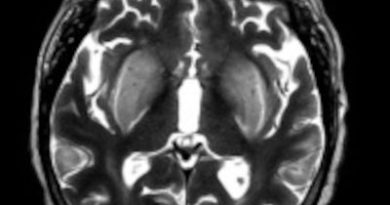

49 yaş, E

DM+, 3 haftadır denge bozukluğu,

1 gün önce başlayan nöbet, yüksek ateş ve bilinç bulanıklığı

Listeria Rhombencephalitis

Listeria rhombensefaliti